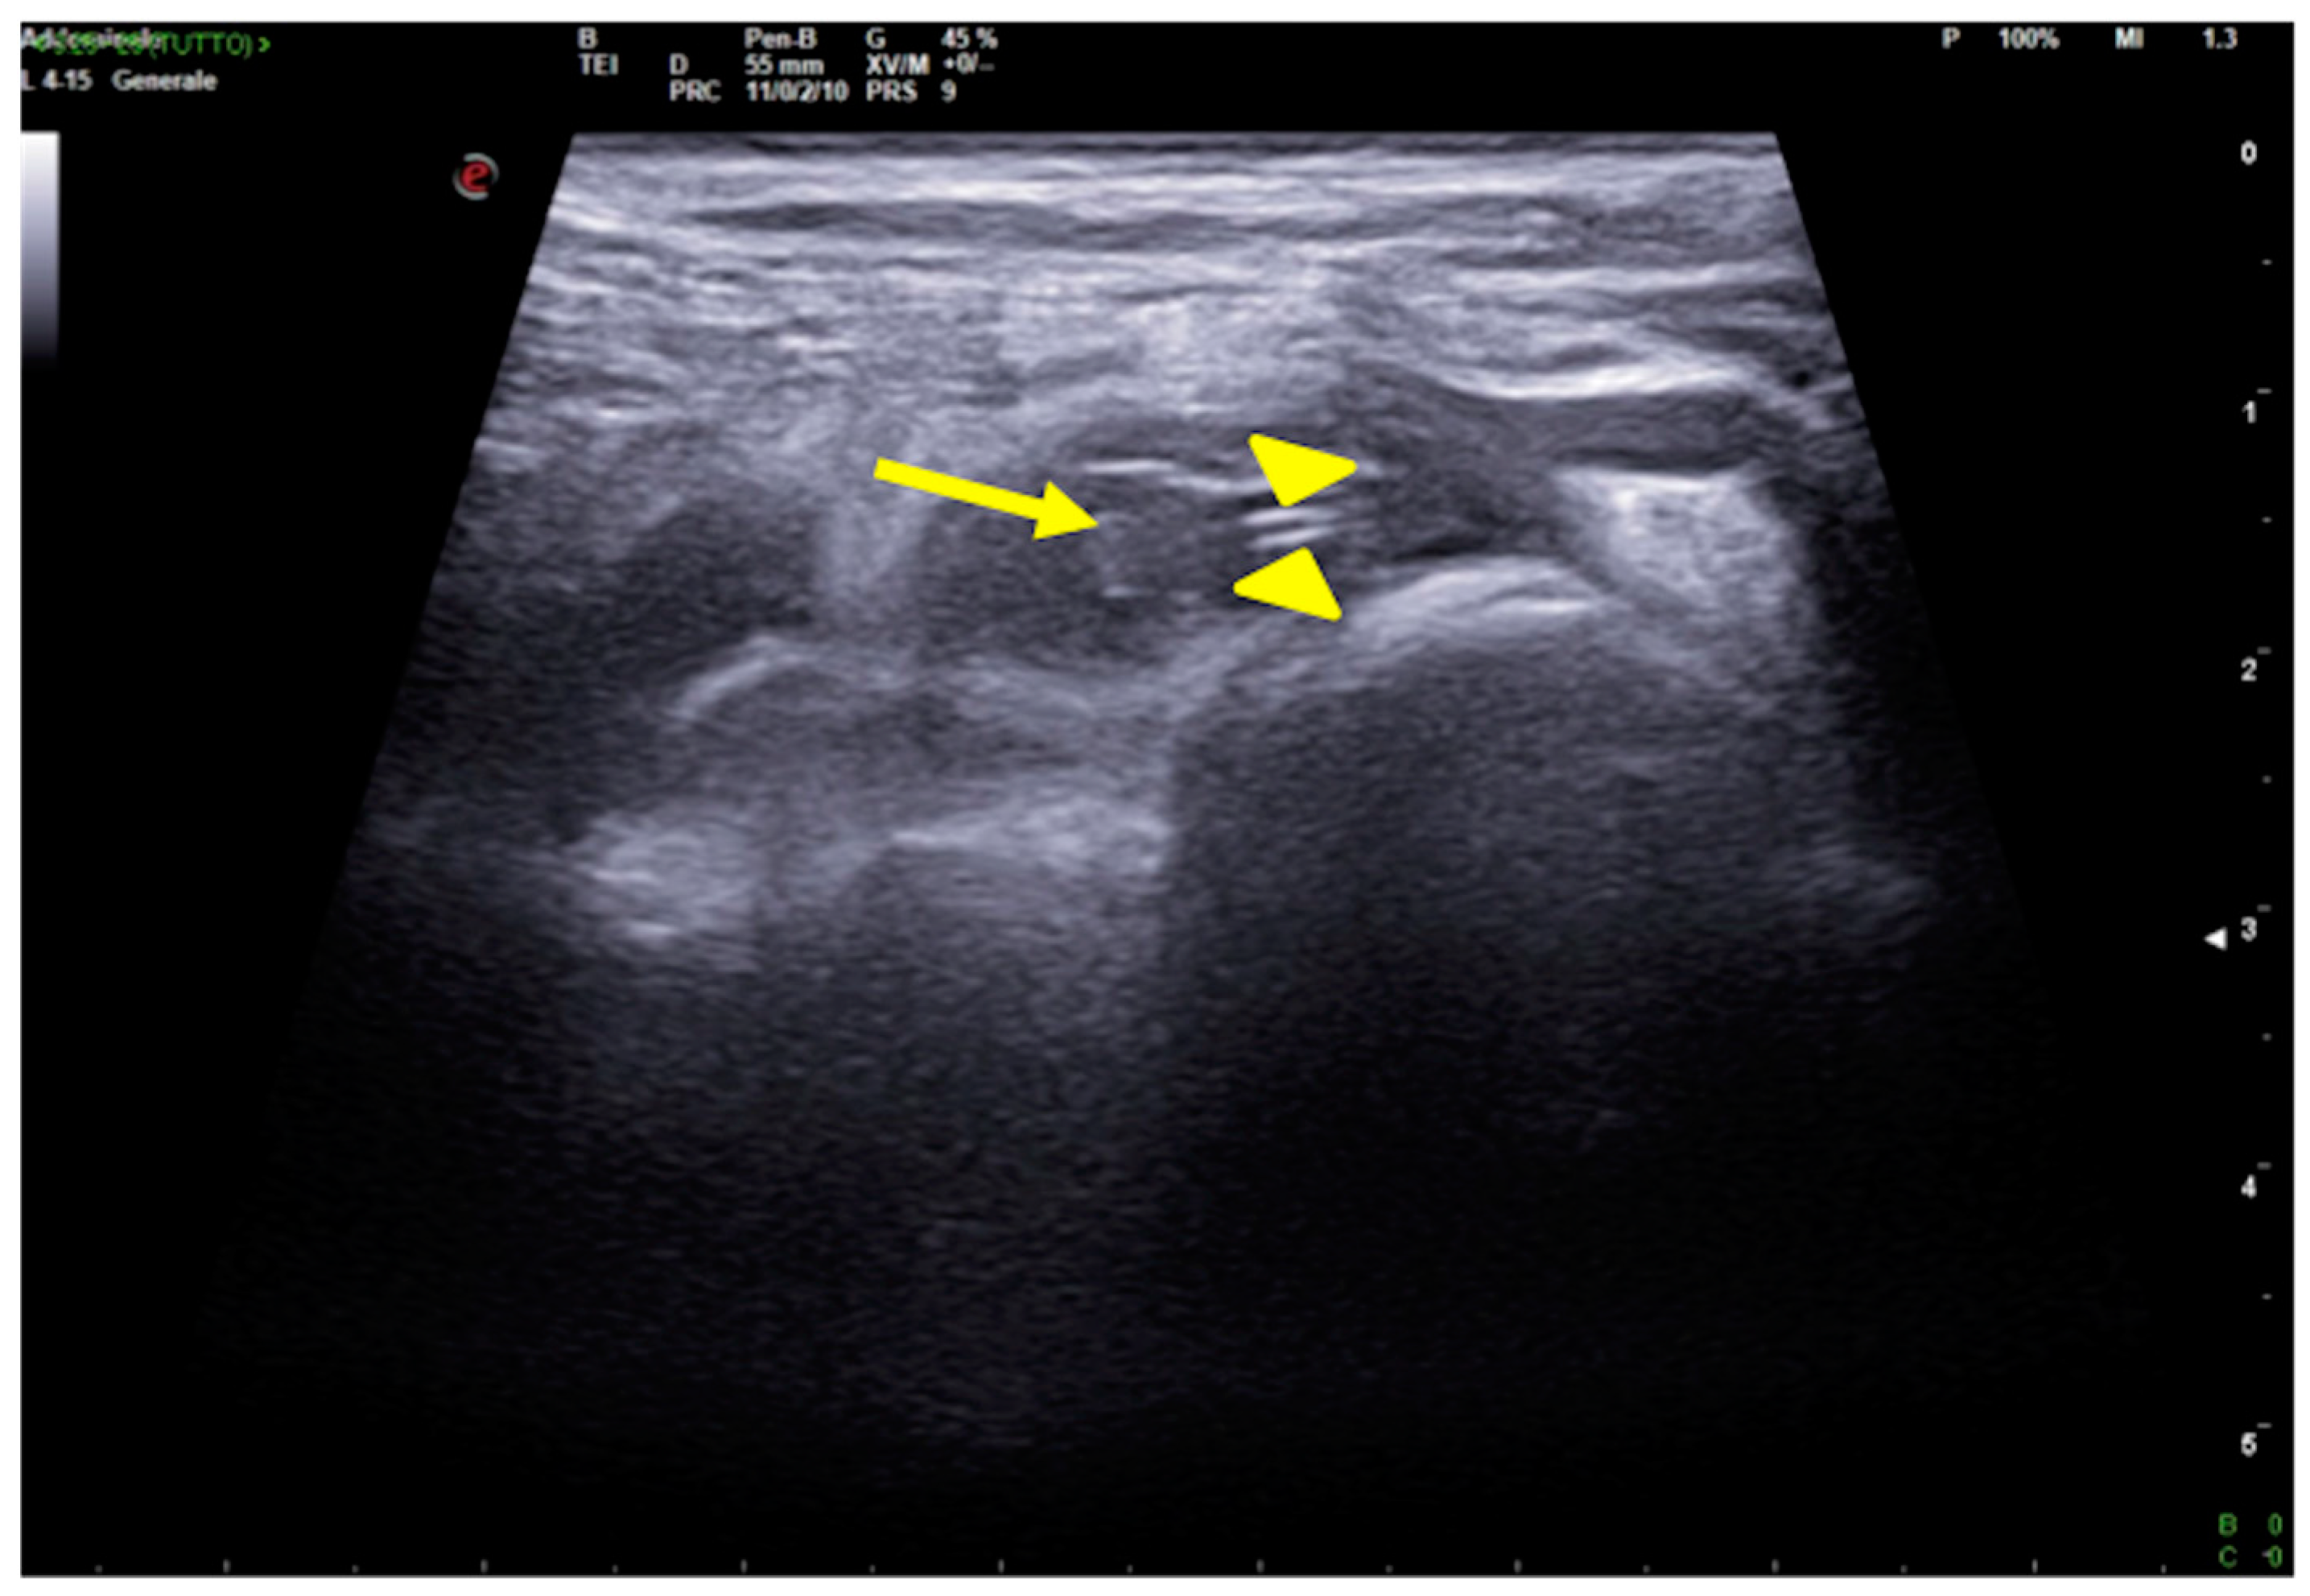

Figure 16.

CVC thrombosis. Right supraclavicular ultrasound exploration highlights the presence of an isocogenic, non-compressible area attributable to thrombosis in the lumen of the subclavian vein (arrow); it also allows visualization of the course of the catheter, visible as a hyperechoic tubular structure (arrowheads).